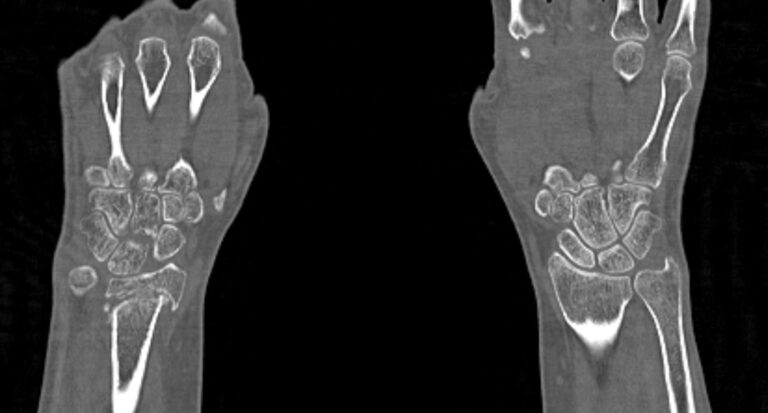

Метод КТ основан на использовании ионизирующего излучения и способности тканей поглощать рентгеновские лучи. Костные ткани обладают высокой плотностью и способны активно поглощать рентгеновские лучи, поэтому они хорошо видны на снимках КТ. В отличие от обычного рентгена компьютерный томограф послойно сканирует исследуемую область в нескольких плоскостях, благодаря чему получаются снимки в мельчайших подробностях. Затем с помощью цифровой обработки данных, полученных при КТ-сканировании, создаются трехмерные модели области исследования.

Таким образом мультиспиральная компьютерная томография позволяет оценить состояние всех структур лучезапястного сустава, выявить травматические повреждения, признаки воспалительных заболеваний, диагностировать аномалии развития и опухолевые образования. При травмах на снимках и трехмерных изображениях хорошо видны фрагменты костных отломков, эти данные используются при подготовке к оперативным вмешательствам. После операции результаты КТ позволяют оценить правильность репозиции костных структур, выявить послеоперационные осложнения, отследить в динамике процесс восстановления тканей.